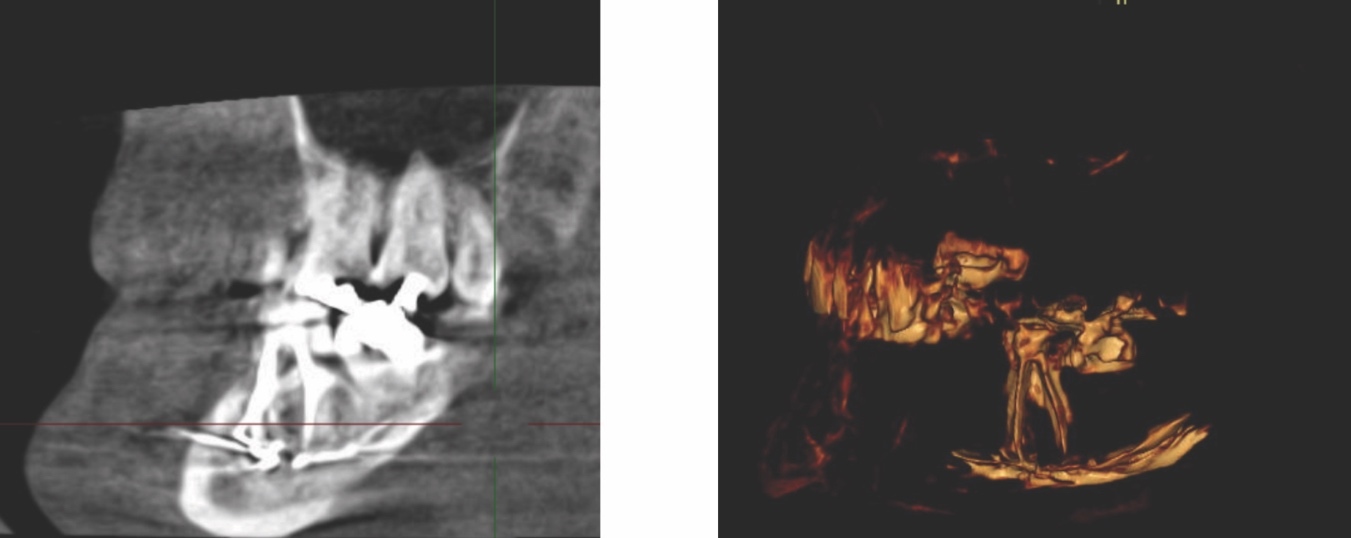

Radiographic examinations consisted of digital orthopantomogram (OPG), peri-apical (PA), and cone beam computed tomography (CBCT) scans. The scans revealed that the lower left first molar root canals were obturated with a radiopaque material, and showed root canal filling extending beyond the apices of the tooth and approximately 5cm along the mandibular canal (Figures 1, 2 and 3).